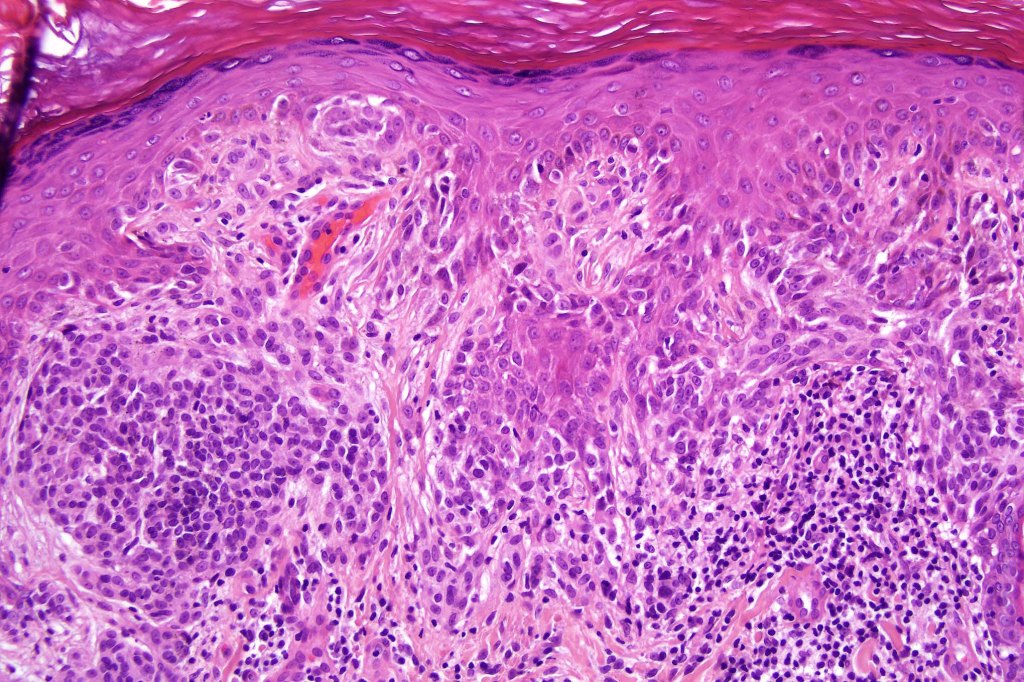

Combined common melanocytic nevus & BAP1-inactivated melanocytoma